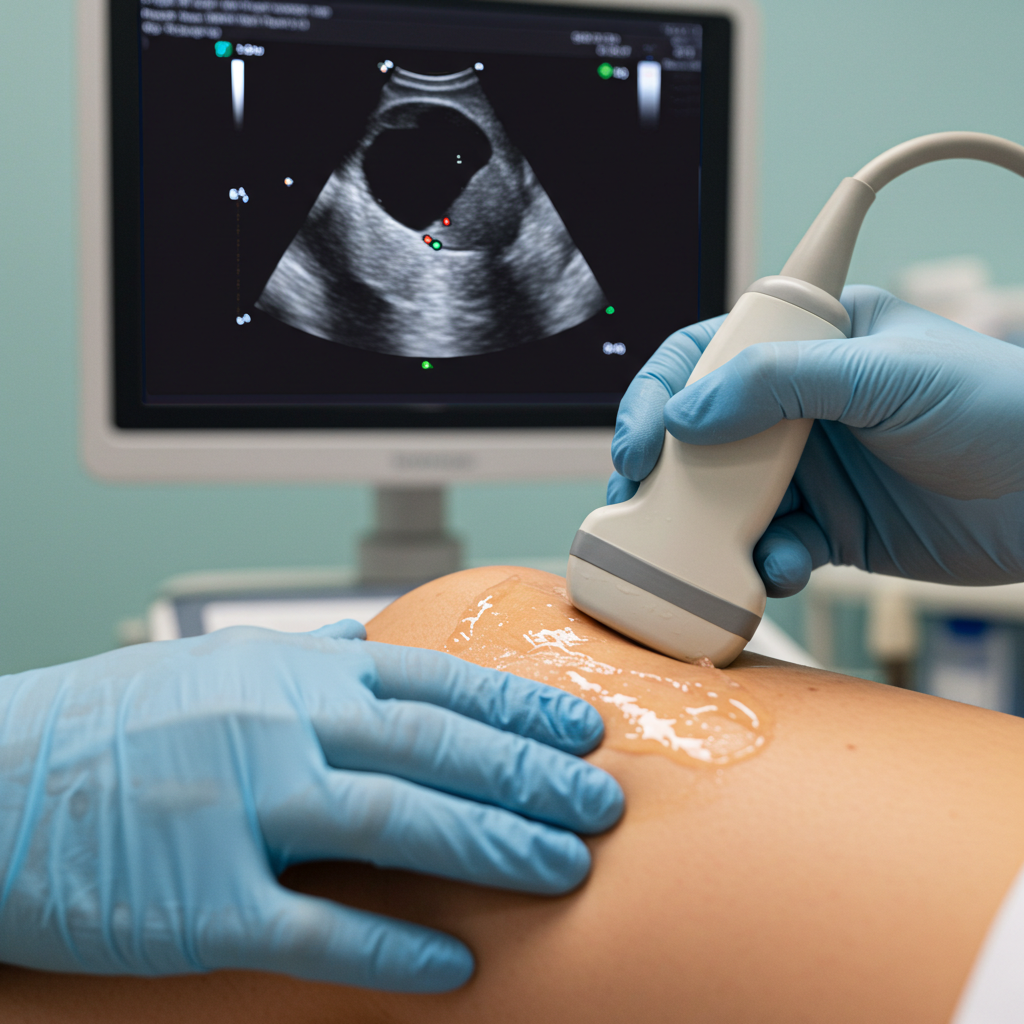

DIAGNOSTIC ULTRASOUND SCAN

Our specialist musculoskeletal sonographers use advanced diagnostic ultrasound to accurately assess conditions like frozen shoulder, knee arthritis, trigger finger, and plantar fasciitis.

This painless, real-time imaging helps us precisely locate the source of your pain and create a personalized treatment plan tailored to your needs.